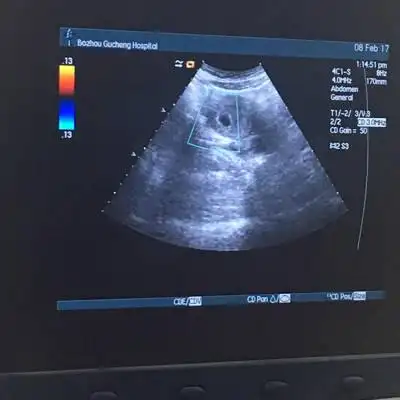

怀孕40天有很小的红色血块流出,查b超显示有孕囊,是先兆流产吗?